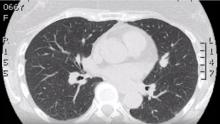

This video shows a robotic lingulectomy and lymphadenectomy in a 62-year-old non-smoker with a history of Dukes' B colorectal adenocarcinoma. The surgeon begins by dissecting the inferior pulmonary ligament, where the station 9 lymph nodes were dissected and sampled. The station 7 lymph nodes were then dissected. The surgeon then moved into the anterior oblique fissure and found a large L11 lymph node that looked malignant and removed that, as well as some L10 nodes. Next, a Gold Tip Tan 45 Stapler with a Leader Catheter was used to divide the lingular artery. The same technique was used to divide the lingular vein and finally the lingular bronchus, with an inflation test. Some L12 nodes were removed. Finally, the lingular segment was divided using an air inflation test to identify the boundaries of the segment, and the segment was removed.